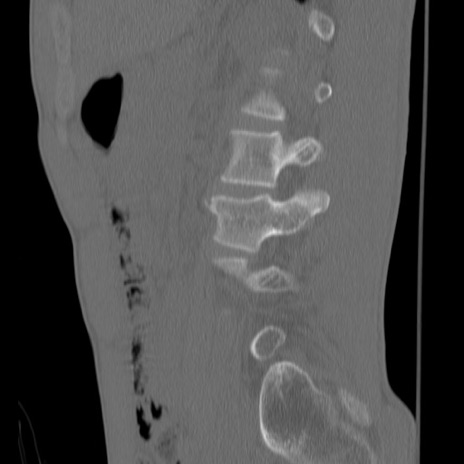

症例3 腰椎CT(矢状断像)

【症例】30歳代男性

【主訴】腰痛

【現病歴】本日旅行先で観光中に、友人と衝突し転倒し受傷。

【身体所見】麻痺なし、右下腿内側前面外側、左下腿内側に知覚鈍麻・しびれ

異常所見と診断は?

腰椎CT